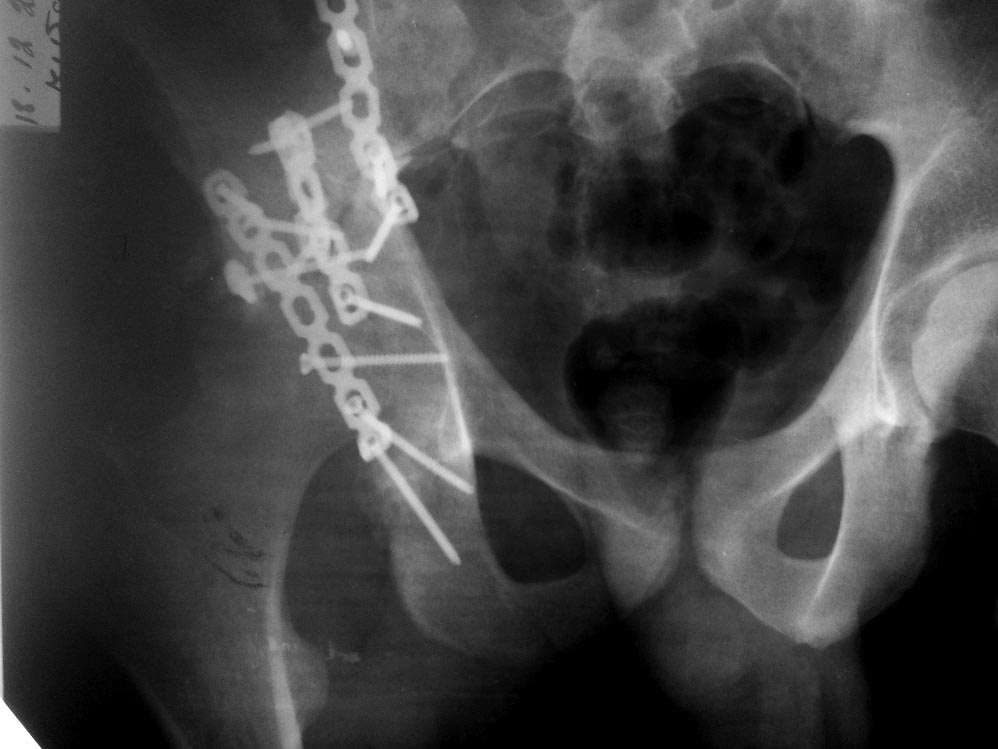

Пациент 19 лет, ДТП в сентябре 2012 г, оперирован поэтапно в др. клинике. В сентябре пациенту первым этапом была проведена операция – МОС лодыжек правой голени, МОС правой бедренной кости. Через 2 недели была проведена операция МОС костей таза и открытое устранение вывиха правого бедра.

Повторная операция – реостеосинтез костей таза была проведена через 1 месяц после первичной. Дз: задний вывих правого бедра (сроки -3 месяца). Асептический некроз головки правой бедренной кости. Неконсолидирующийся перелом средней трети правой бедренной кости, неправильно консолидирующийся перелом лодыжек правой голени с подвывихом стопы кзади, передняя медиальная нестабильность правого К/С. Сгибательно-приводящая контрактура правого Т/Б сустава, сгибательно-разгибательная контрактура правого К/С, эквинусная установка в правой стопе на фоне пост-операционного пареза

Перелом вертлужной впадины отличается от “переломов таза” не только исследованием, но также тактикой. По классификации Летурнеля расположение линии перелома характерно для поперечного перелома вертлужной впадины, но наличие шурупов в заднем крае (второй снимок) и вывих бедра подтверждают, что здесь сочетание заднего края с поперечным переломом.

Надо сделать снимки Judet и при возможности КТ. А 3Д снимки покажут общий вид, но детали в области суставов дает срезы КТ.

Через задний доступ смогли сделать частичную репозицию, а здесь напрашивался двойной доступ спереди и сзади. Репозиция в положении на боку затруднительна, и вытяжение за перекладину над операционным столом облегчило бы репозицию.

Здесь пара случаев, где обычный поперечный перелом зафиксирован задним доступом и второй поперечный перелом в сочетании задней стенки, где на КТ слева в шейке обнаружен перелом без смещения, который зафиксирован профилактически.